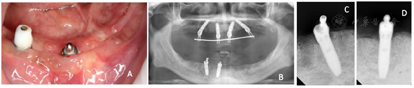

术后1个月(2017年3月22日)复诊上下颌术区牙龈黏膜愈合良好,下颌复合基台及球基台周围可见软垢滞留,进行口腔卫生健康教育指导(图8A)。术后3个月(2017年5月17日)复诊X线检查示上下颌种植体骨结合良好(图8B、C)

①上颌取模一期种植术后5个月后(2017年6月29日)复诊,检查上下颌临时义齿完成,X线示种植体周围骨结合良好,取下过渡义齿,取模拟制作上颌钛支架支持的树脂人工牙种植修复(图9)。拍摄下颌CT检查评估左下颌区牙槽骨愈合良好(图10)。

②左下颌种植一期手术:2017年7月15日局麻下于32、35区植入2枚Nobel speedy4x13mm种植体,旋入复合基台;取下42原放置的球基台更换为复合基台,制取下颌开窗式种植修复印模(图11)。